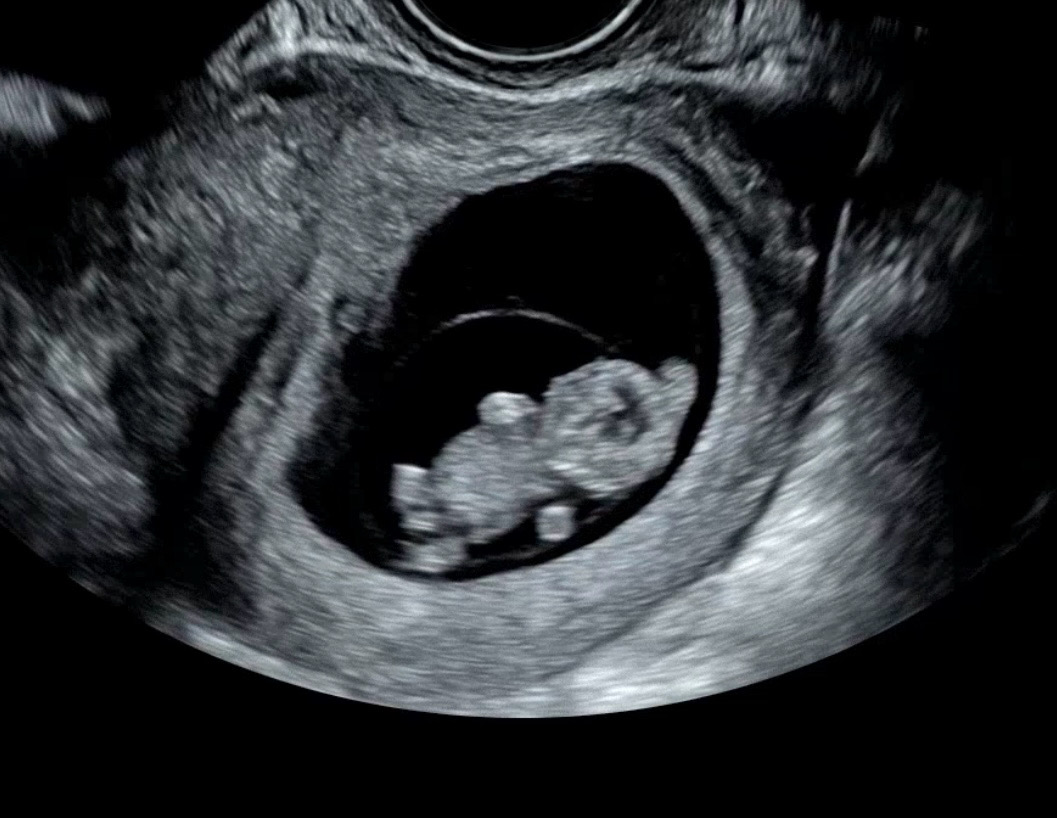

10주 2일차 하리보!

10주 2일된 예비아빠입니다. 우리 아가에요! 헤헤 귀엽죠? 주간엔 떨어져 있어 아내에게 미안한 마음이 늘 있는데 아가는 쑥쑥 크고 아내도 혼자 씩씩하게 지내는 모습이 너무 고맙네요.. 더 잘해야겠어요! 다들 건강하세용!